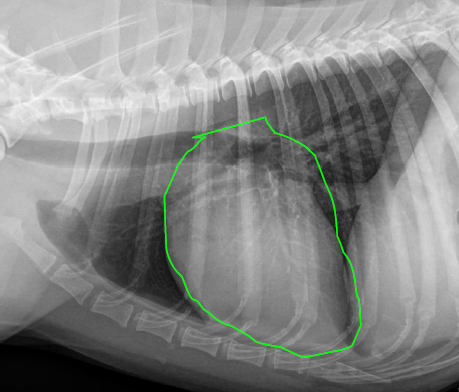

Lateral

12 to 2

Left atrium

Aortic arch

Ascending aorta

Right auricle

Pulmonary artery

Right ventricle

Cardiac silhouette